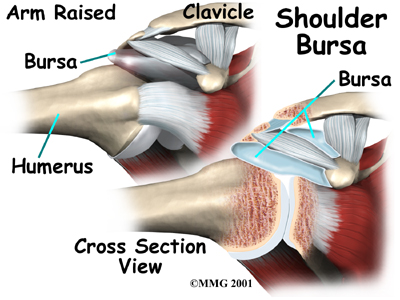

The part of the scapula that connects to the lateral shoulder is called the acromion. A bursa is located between the acromion and the rotator cuff tendons. A bursa is a lubricated sac of tissue that cuts down on the friction between two moving parts. Bursae are located all over the body where tissues must rub against each other. In this case, the bursa protects the acromion and the rotator cuff from grinding directly against each other.